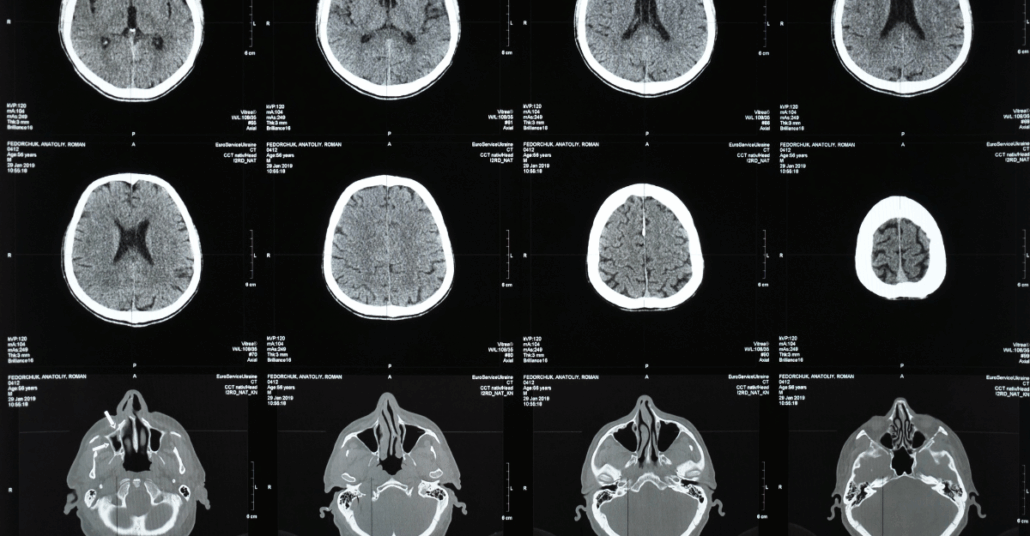

- Imaging Scans (CT and MRI): A CT scan is often used first to look for bleeding, bruising, or skull fractures. An MRI can provide a more detailed view of the brain tissue and may detect subtle injuries that a CT scan misses. However, it is important to note that a mild TBI or concussion will often not show up on these scans, even though the injury is real.